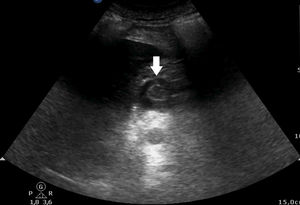

Pocos días después, el paciente inició un dolor abdominal severo (8 escala EVA). A la exploración, el abdomen estaba distendido y timpánico. La sonda nasogástrica se colocó en aspiración, pero fue improductiva. Se realizó una ecografía abdominal colocando la sonda transversal en región abdominal entre espigastrio y mesogastrio. Ahí se visualizó el antro gástrico dilatado, con contenido (ecogénico) y sin peristaltismo (fig. 1). El estudio se completó con TAC abdominal que confirmó la gran dilatación gástrica (fig. 2) y la presencia de la sonda nasogástrica en esófago. Se recolocó dicha sonda nasogástrica en aspiración, obteniéndose 1,5 litros de contenido gástrico. Tras ello, se comprobó en la misma ventana abdominal referida de ecografía, que el estomago estaba vacío a través del signo del ojo de buey (fig. 3). El paciente fue dado de alta después de 6 días.